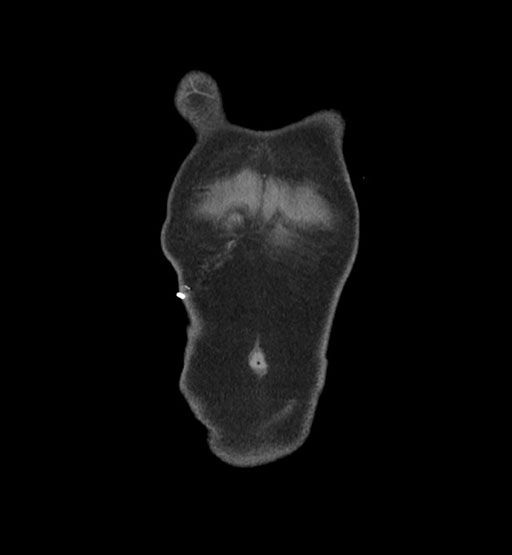

MRI T1

MRI T2

Imaging analysis

Based on initial findings, which issue(s) would you be most concerned about?